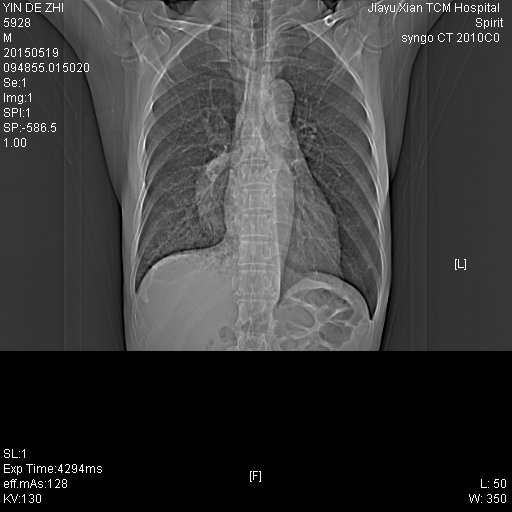

CT50471:男,65Y

【一周后复查片】 曾食管癌病史,各位老师专家帮看下

)食管癌并食管右侧胸腔瘘,右下肺感染。2)双侧少量胸腔积液。3)心包少量积液。4)肺气肿

1)食管癌并食管右侧胸腔瘘,右下肺感染。2)双侧少量胸腔积液。3)心包少量积液。4)肺气肿

1)食管癌并食管右侧胸腔瘘,右下肺感染。2)双侧少量胸腔积液。3)心包少量积液。4)肺气肿。支持!

食管癌引起食管支气管瘘,继发肺脓肿、肺炎症、胸腔积液。支持。

食管癌引起食管支气管瘘,继发肺脓肿、肺炎症、胸腔积液。

1)食管癌术后食管右侧胸腔瘘,右下肺感染。2)双侧少量胸腔积液。3)心包少量积液。4)肺气肿。

1)食管癌并食管右侧胸腔瘘,右下肺感染。2)双侧少量胸腔积液。3)心包少量积液。4)肺气肿。